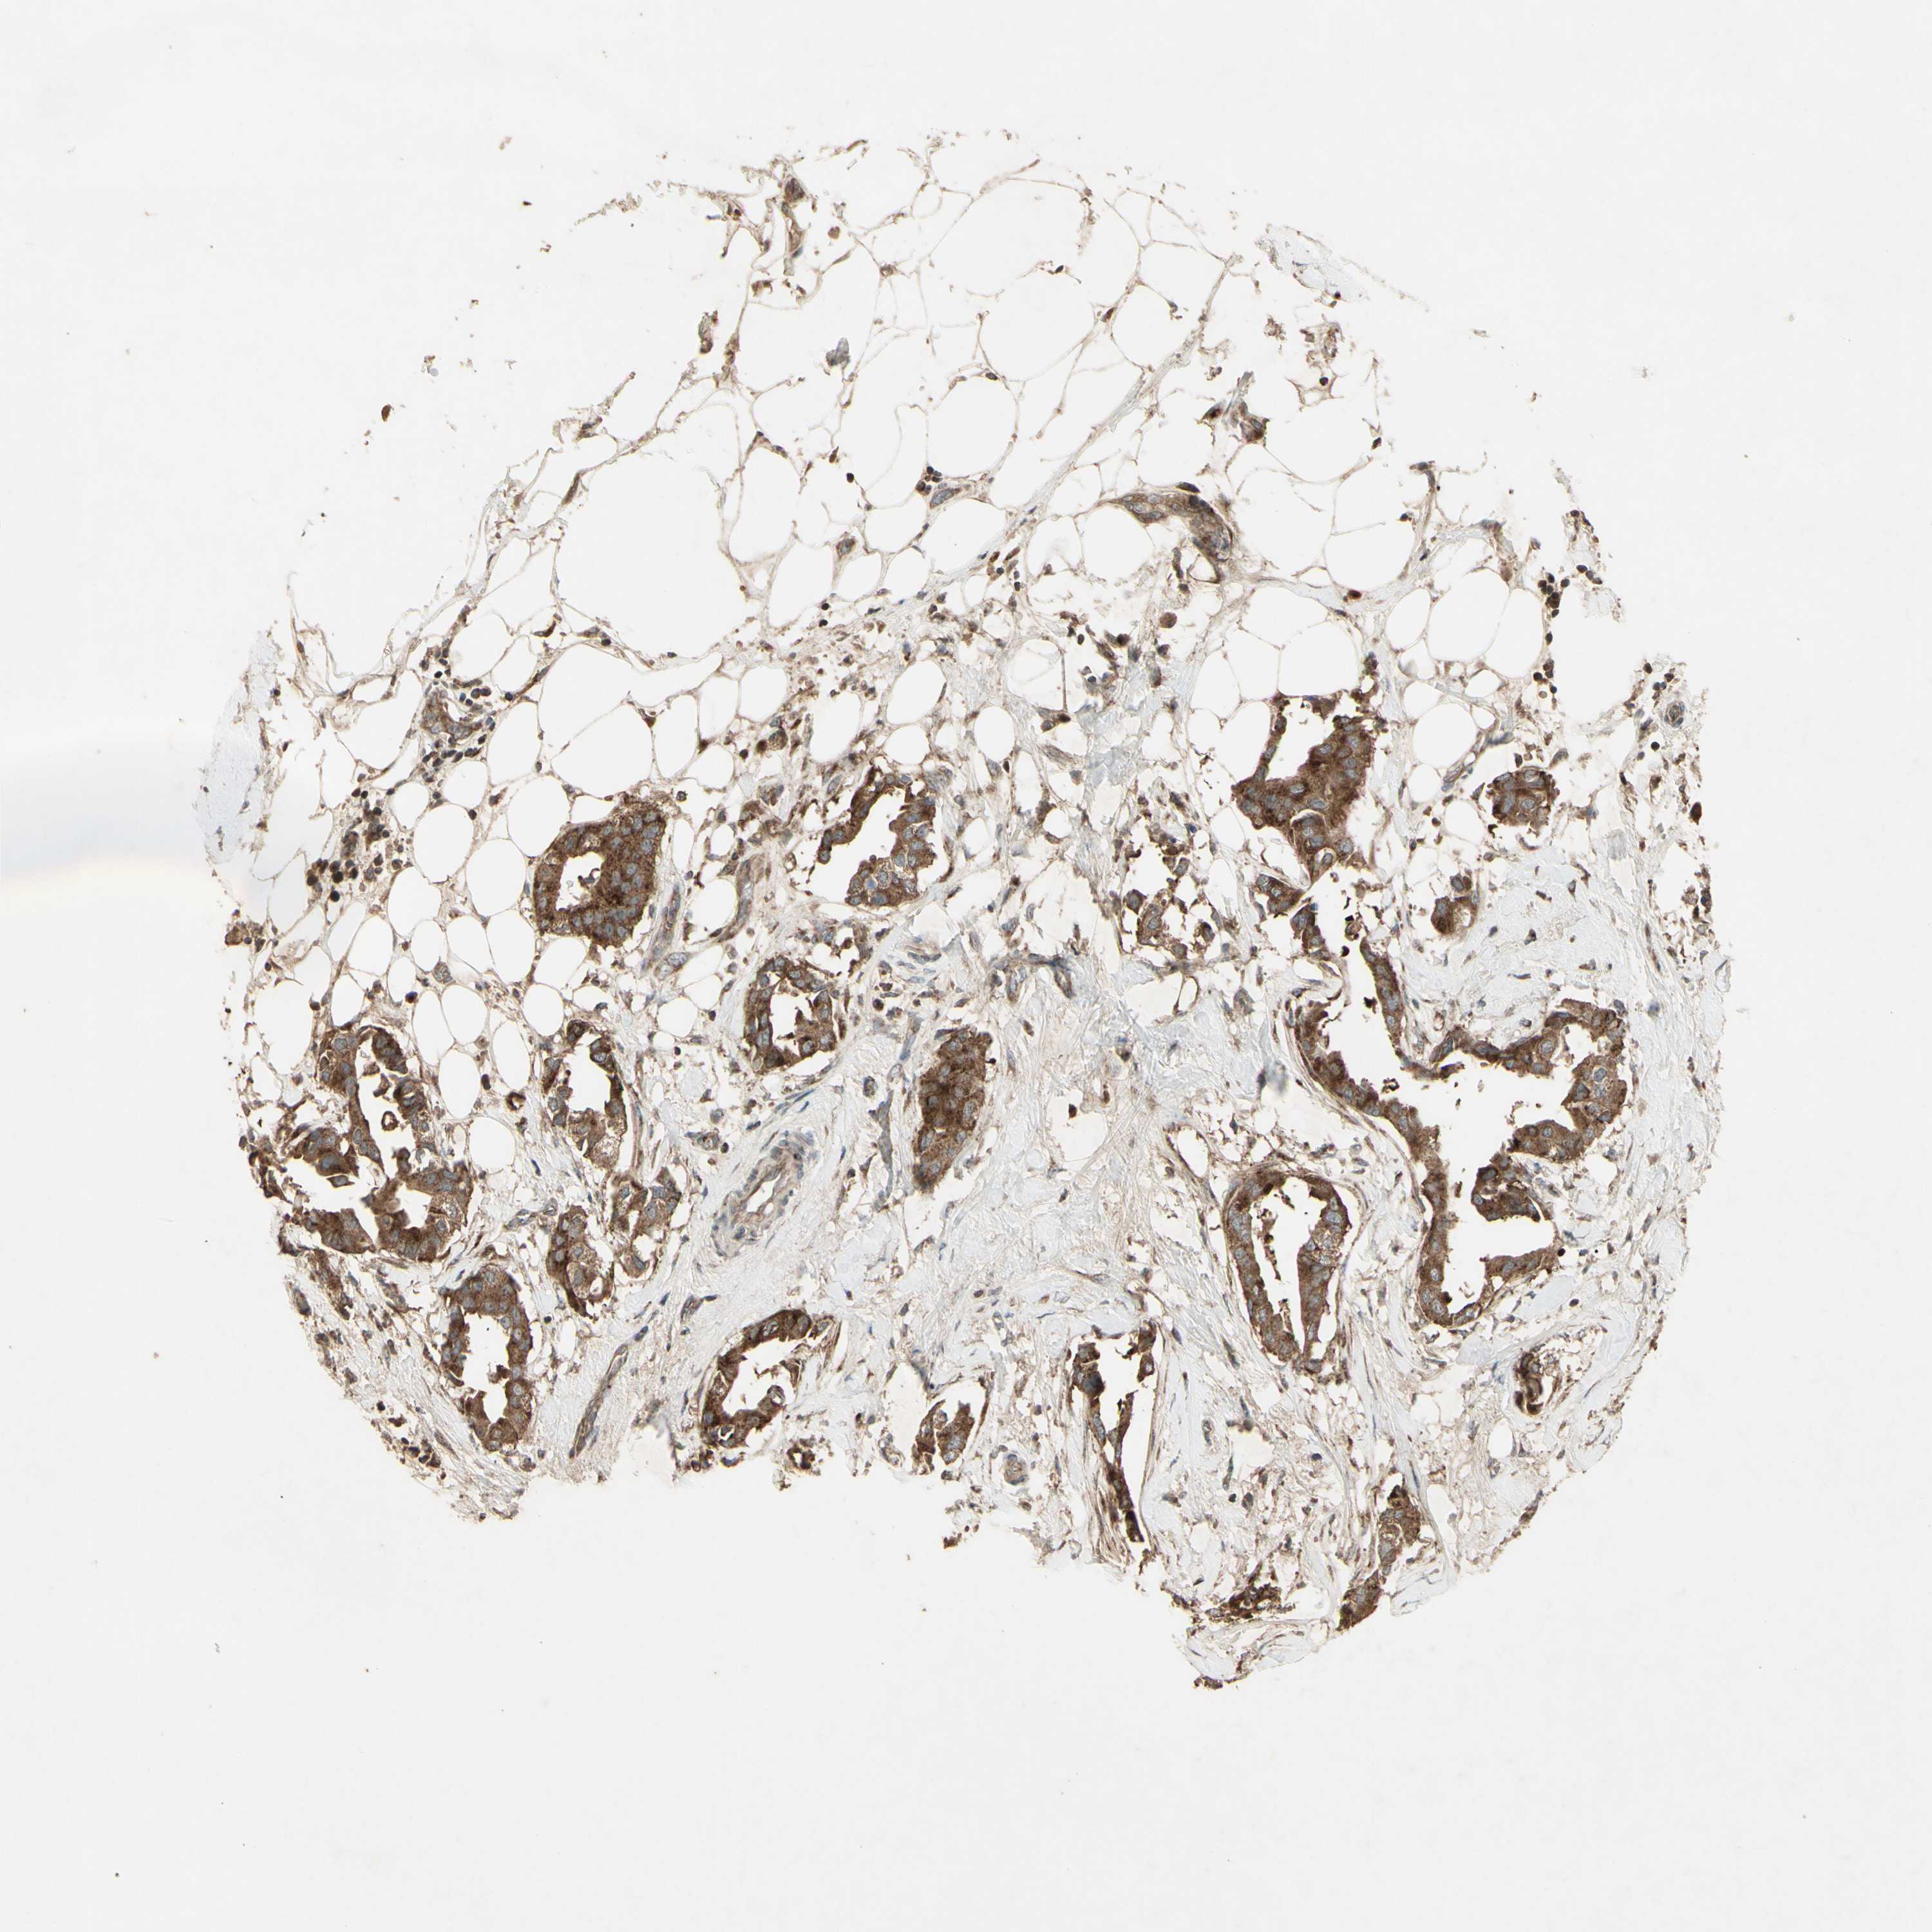

BRCA TCGA BRCA VALIDATION PROTEIN EXPRESSION

Breast cancer

Human cancer